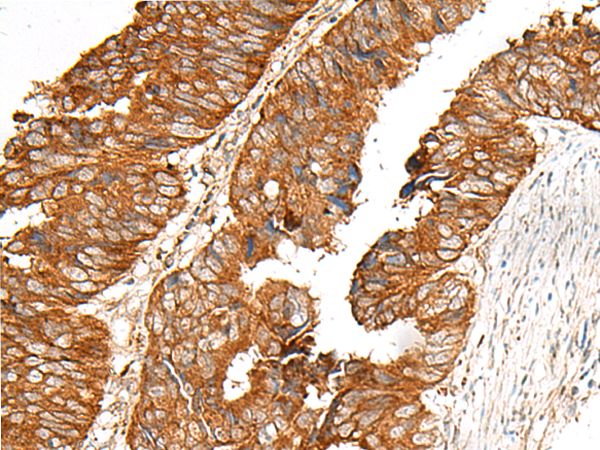

Applications:

ELISA, IHC

IHC positive control:

Human cervical cancer and Human colorectal cancer

IHC Recommend dilution:

30-150